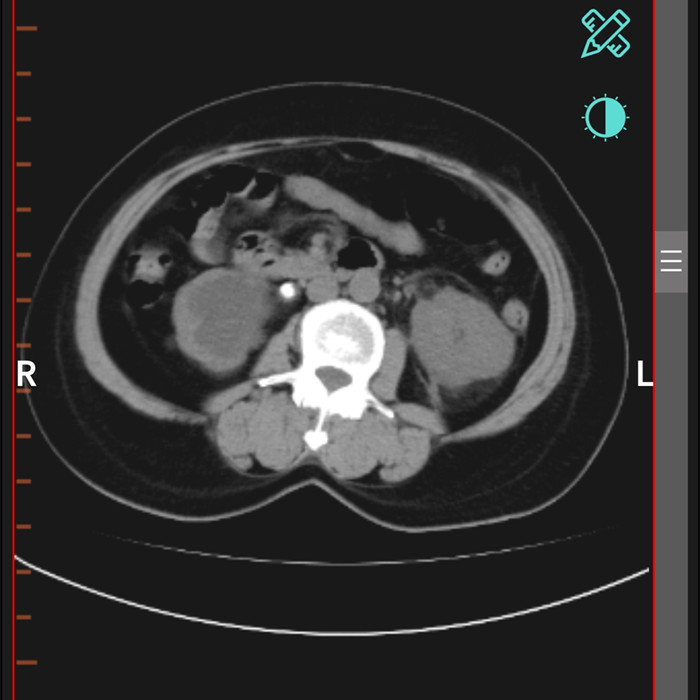

柴女士,62歲,北川縣擂鼓鎮(zhèn)人,因腰右側(cè)疼痛難忍,她來到北川羌族自治縣人民醫(yī)院就診,經(jīng)檢查提示,柴女士右輸尿管上段結(jié)石嵌頓引起重度腎積水。

“要及時解除梗阻,可以行腹腔鏡輸尿管切開取石術(shù)取代開放手術(shù)。”在朱劍勇的帶領下,這支剛剛成立的“泌尿外科團隊”,僅用了一個半小時就完成了手術(shù)?!案骨荤R輸尿管切開取石術(shù)創(chuàng)傷小,患者腰腹部只有3個戳孔,術(shù)后恢復快?!敝靹τ抡f。